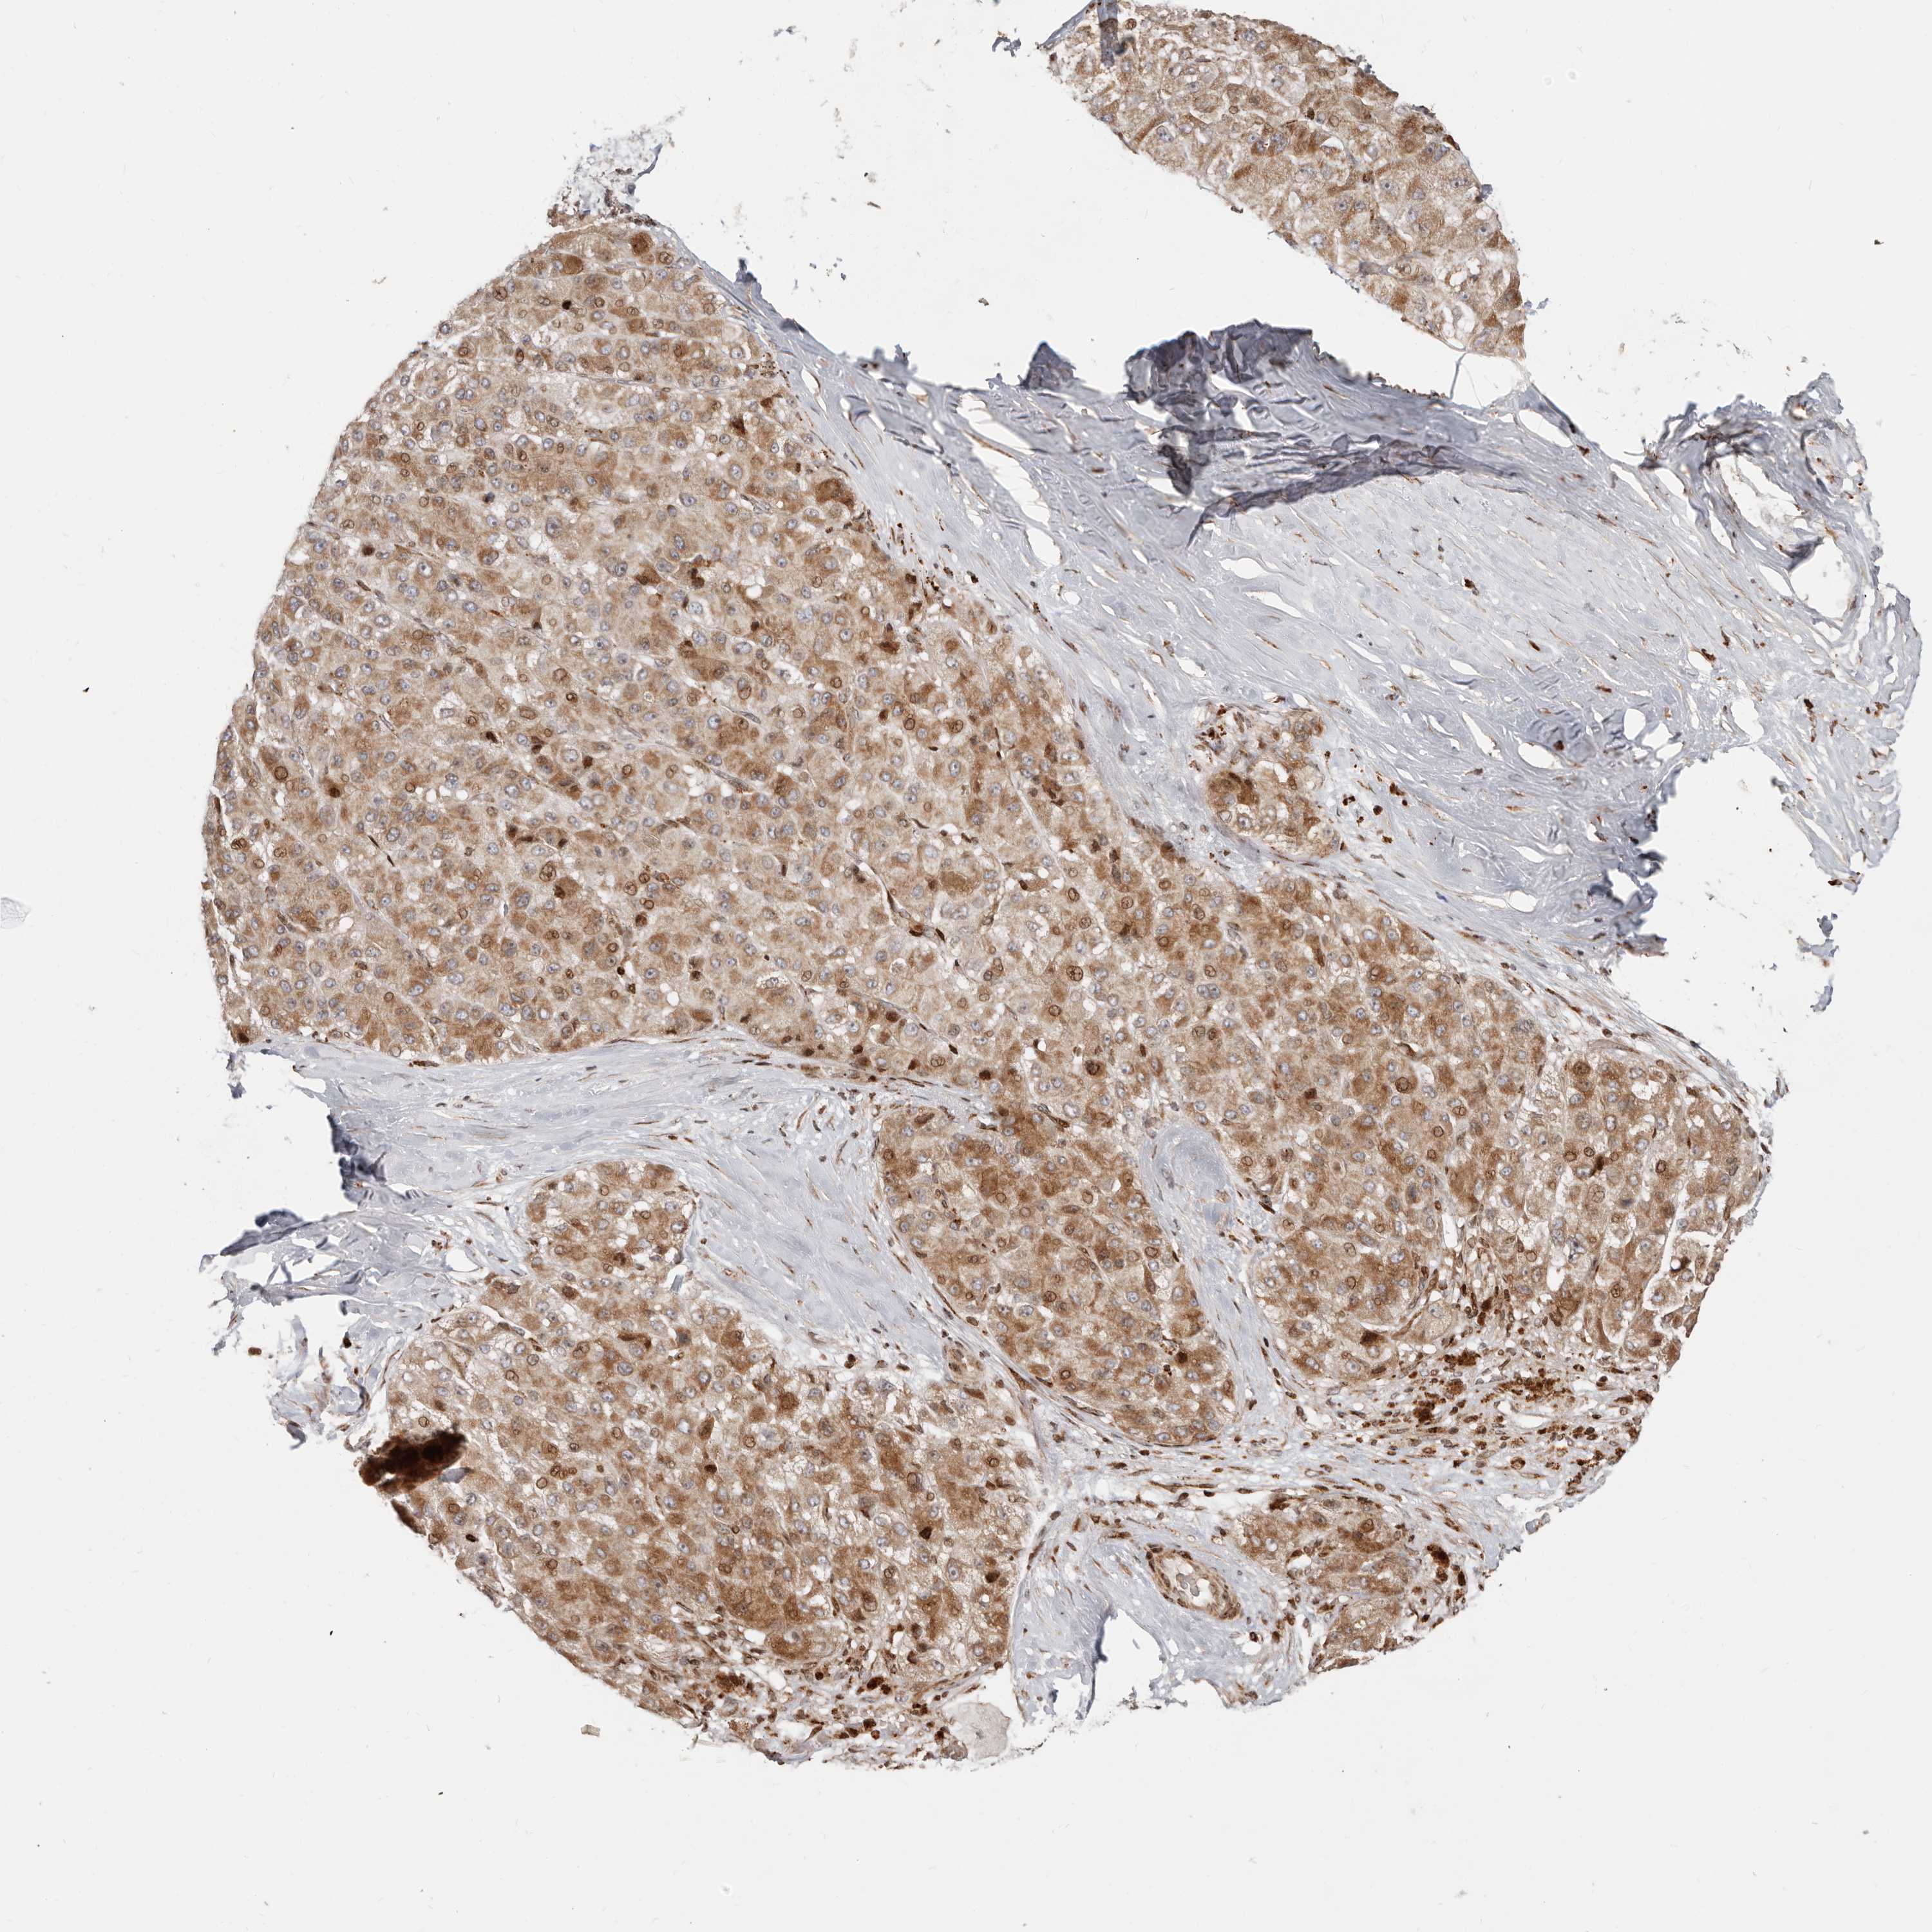

LIVER CANCER - Protein expressioni

A mouse-over function shows sample information and annotation data. Click on an image to view it in a full screen mode. Samples can be filtered based on level of antibody staining by selecting one or several of the following categories: high, medium, low and not detected. The assay and annotation is described here.

Note that samples used for immunohistochemistry by the Human Protein Atlas do not correspond to samples in the TCGA dataset.

Antibody stainingi

Antibody staining in the annotated cell types in the current human tissue is reported as not detected, low, medium, or high, based on conventional immunohistochemistry profiling in selected tissues. This score is based on the combination of the staining intensity and fraction of stained cells.

Each image is clickable and will lead to virtual microscopy that enables deeper exploration of all samples and also displays staining intensity scores, fraction scores and subcellular localization as well as patient and tissue information for each sample.

Antibody HPA019356

Antibody HPA029461

Staining

High

Medium

Low

Not detected

Intensity

Strong

Moderate

Weak

Negative

Quantity

>75%

75%-25%

<25%

None

Location

Nuclear

Cytoplasmic/membranous

Cytoplasmic/membranous,nuclear

Cholangiocarcinoma

Carcinoma, Hepatocellular, NOS